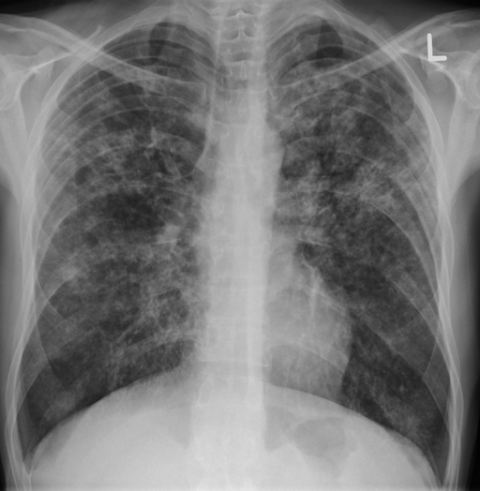

In this study in Bandung city, Indonesia, we followed up 590 people with diabetes who had no evidence of TB at baseline. Within a follow-up time of approximately 3.5 years, 11 people were diagnosed with TB, as established through asking about symptoms, as well as chest x-ray and sputum examination.